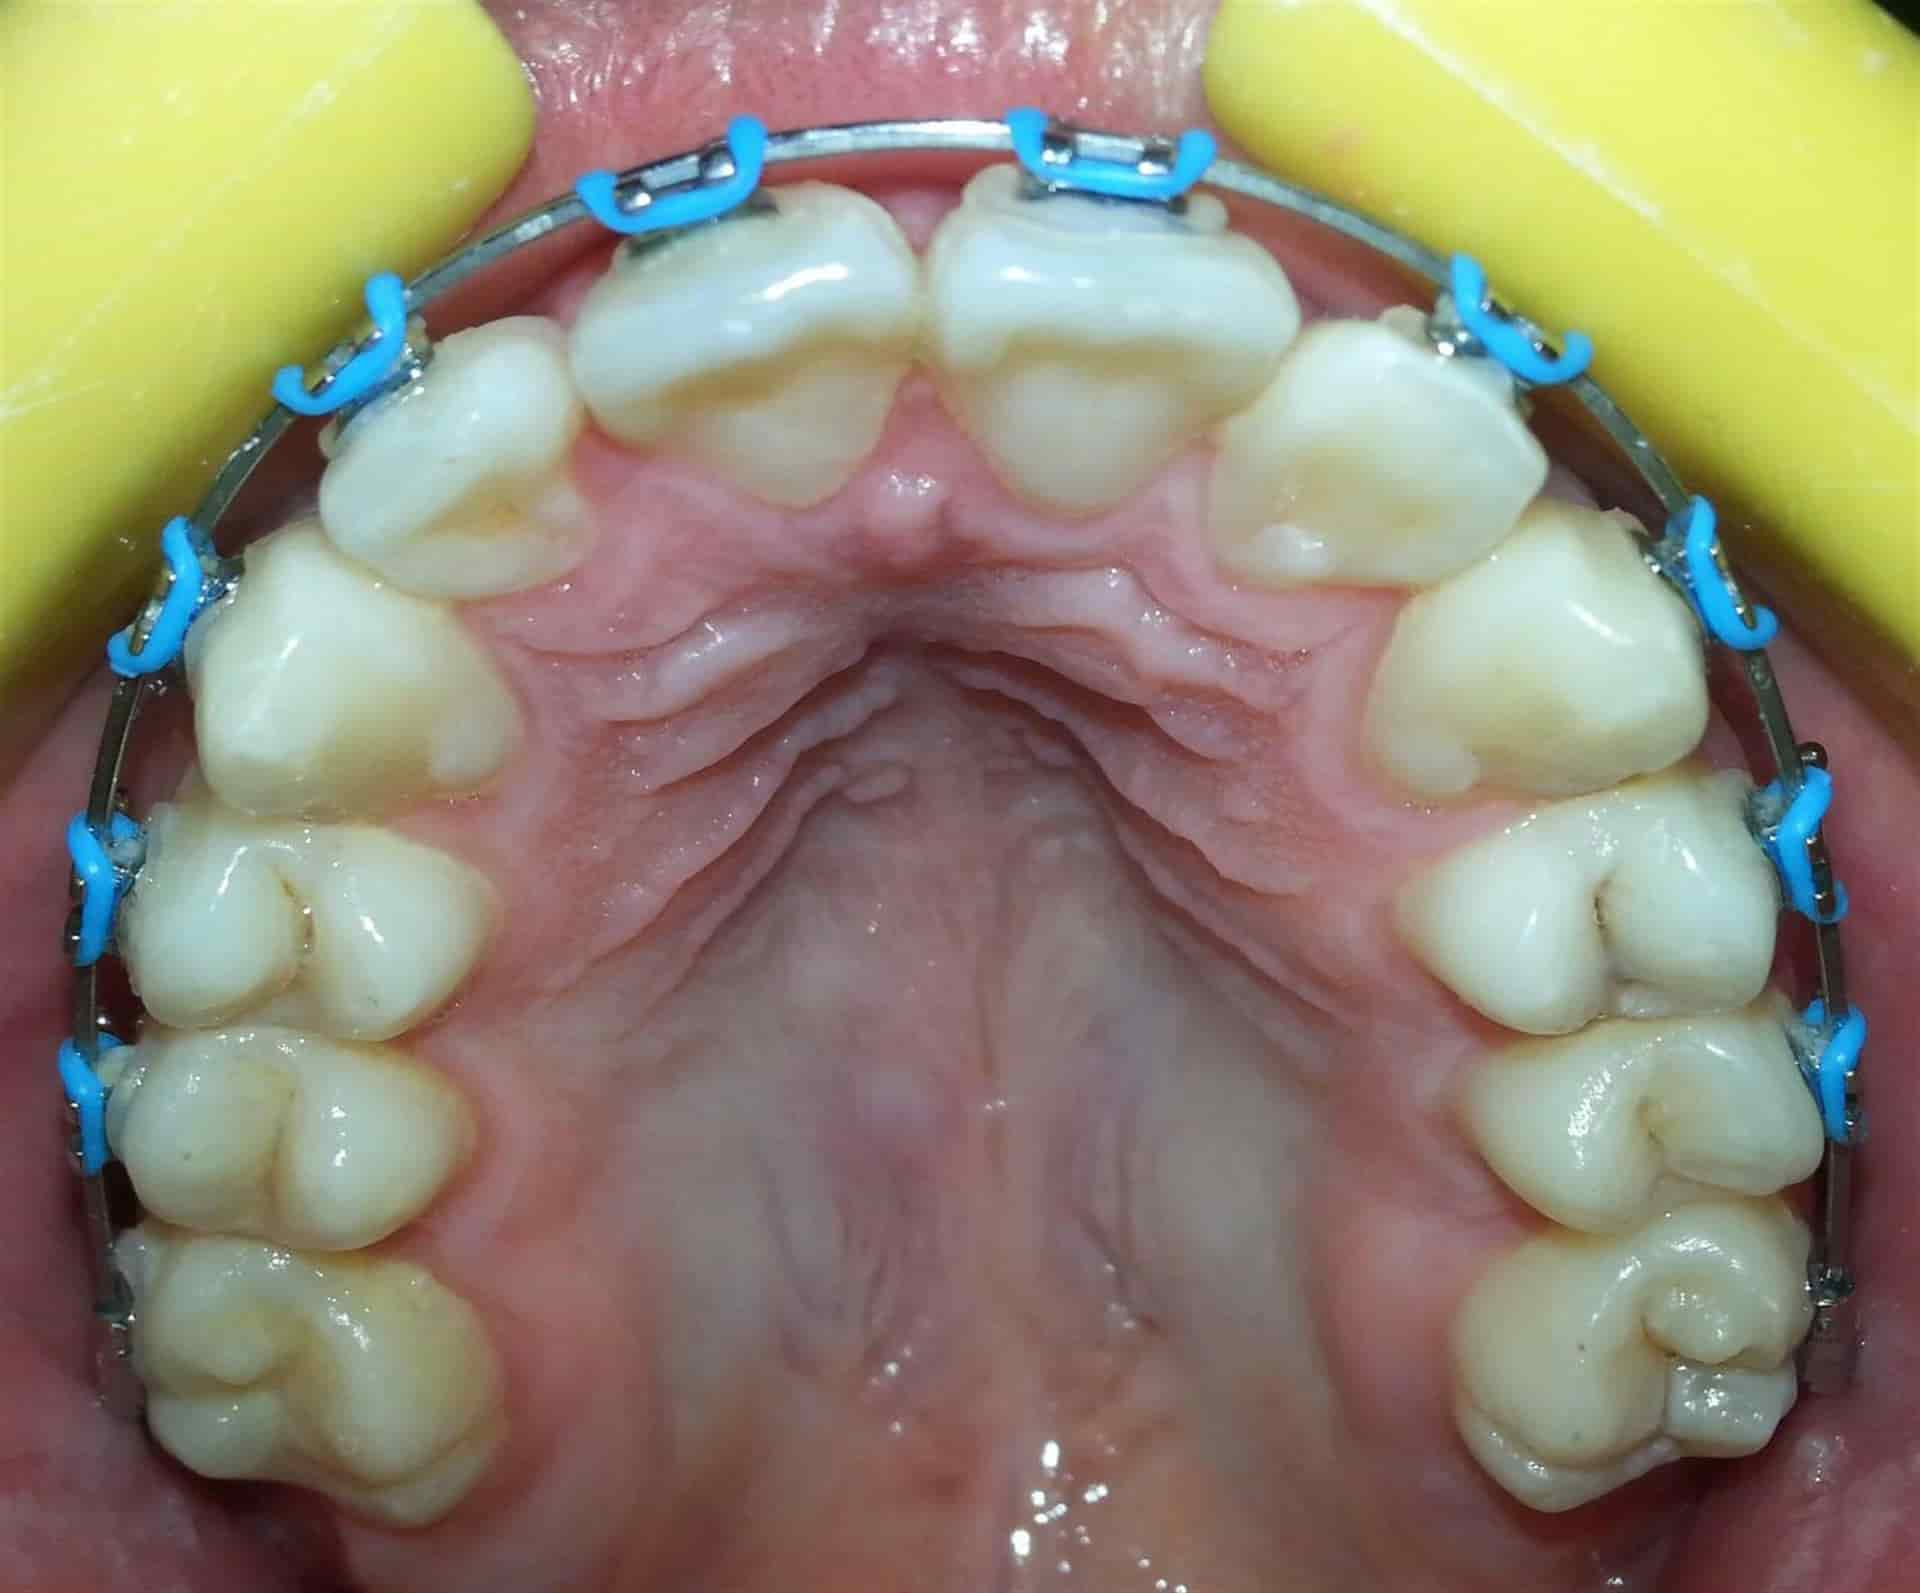

Un mal tratamiento de brackets puede llevar a provocar la pérdida de piezas dentales e incluso cambios en la estructura ósea del rostro.

Incluso señaló que un mal tratamiento de brackets puede llevar a provocar la pérdida de piezas dentales e incluso cambios en la estructura ósea del rostro.

Mencionó que es regular recibir pacientes que se dicen cansados de no notar cambios con sus antiguos médicos y al momento de revisar lo primero que se encuentra es con piezas de adorno que en ocasiones pueden llegar a ser piezas de brackets piratas.

"Cuando yo comienzo a consultar a pacientes que vienen de esos lugares me dicen que están cansados de no ver cambios, al momento de revisar me doy cuenta que faltan brackets, los que dicen brackets por 700 pesos, muchos van a cursos ya aprenden lo básico que es poner un bracket, pero para esto no tienen los conocimientos de ortodoncia, entonces el bracket no es mágico, quien hace el trabajo es el ortodoncista”, explicó.